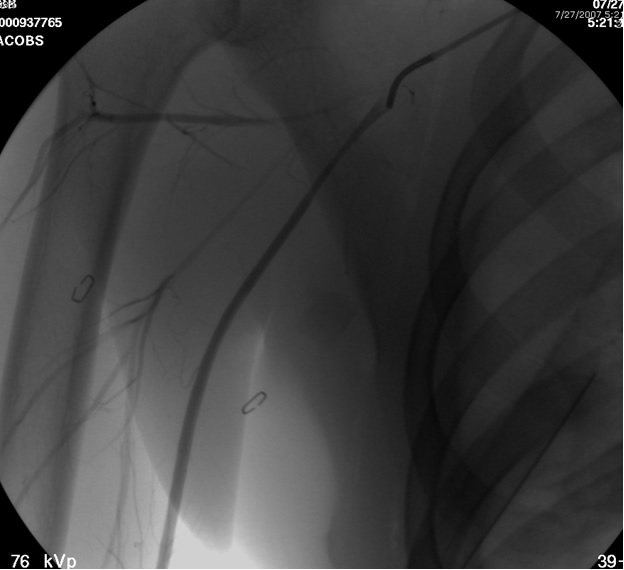

The patient is positioned supine with the ipsilateral upper extremity prepped out at a 90º angle and with both groins and chest prepped in as well. The right femoral artery is percutaneously engaged in a standard Seldinger technique with a standard short 5F sheath. We utilize an 0.035 inch hydrophilic angled Glidewire® (Terumo Medical Corporation, Somerset, NJ), which is brought up into the ascending aorta and followed with a JR4(C.R. Bard Inc. Murray Hill, NJ) catheter. The C-arm is positioned in a 25º LAO view to “open the arch” and the aortogram is commenced delineating the arch and arch vessel anatomy. Gentle traction and pullback on the catheter allows us to engage the target arch vessel, selectively advancing the Glidewire into the appropriate vessel. Next, once the wire is placed far distally the catheter is gently advanced into the appropriate vessel where selective angiograms are performed (Figure 1). Inability to traverse the transected subclavian artery may mandate a retrograde transbrachial approach.

![]() |

| Figure 2: Post deployment of angled glide wire and JR4 catheter past the transected subclavian artery revealing patent vessel distally. |